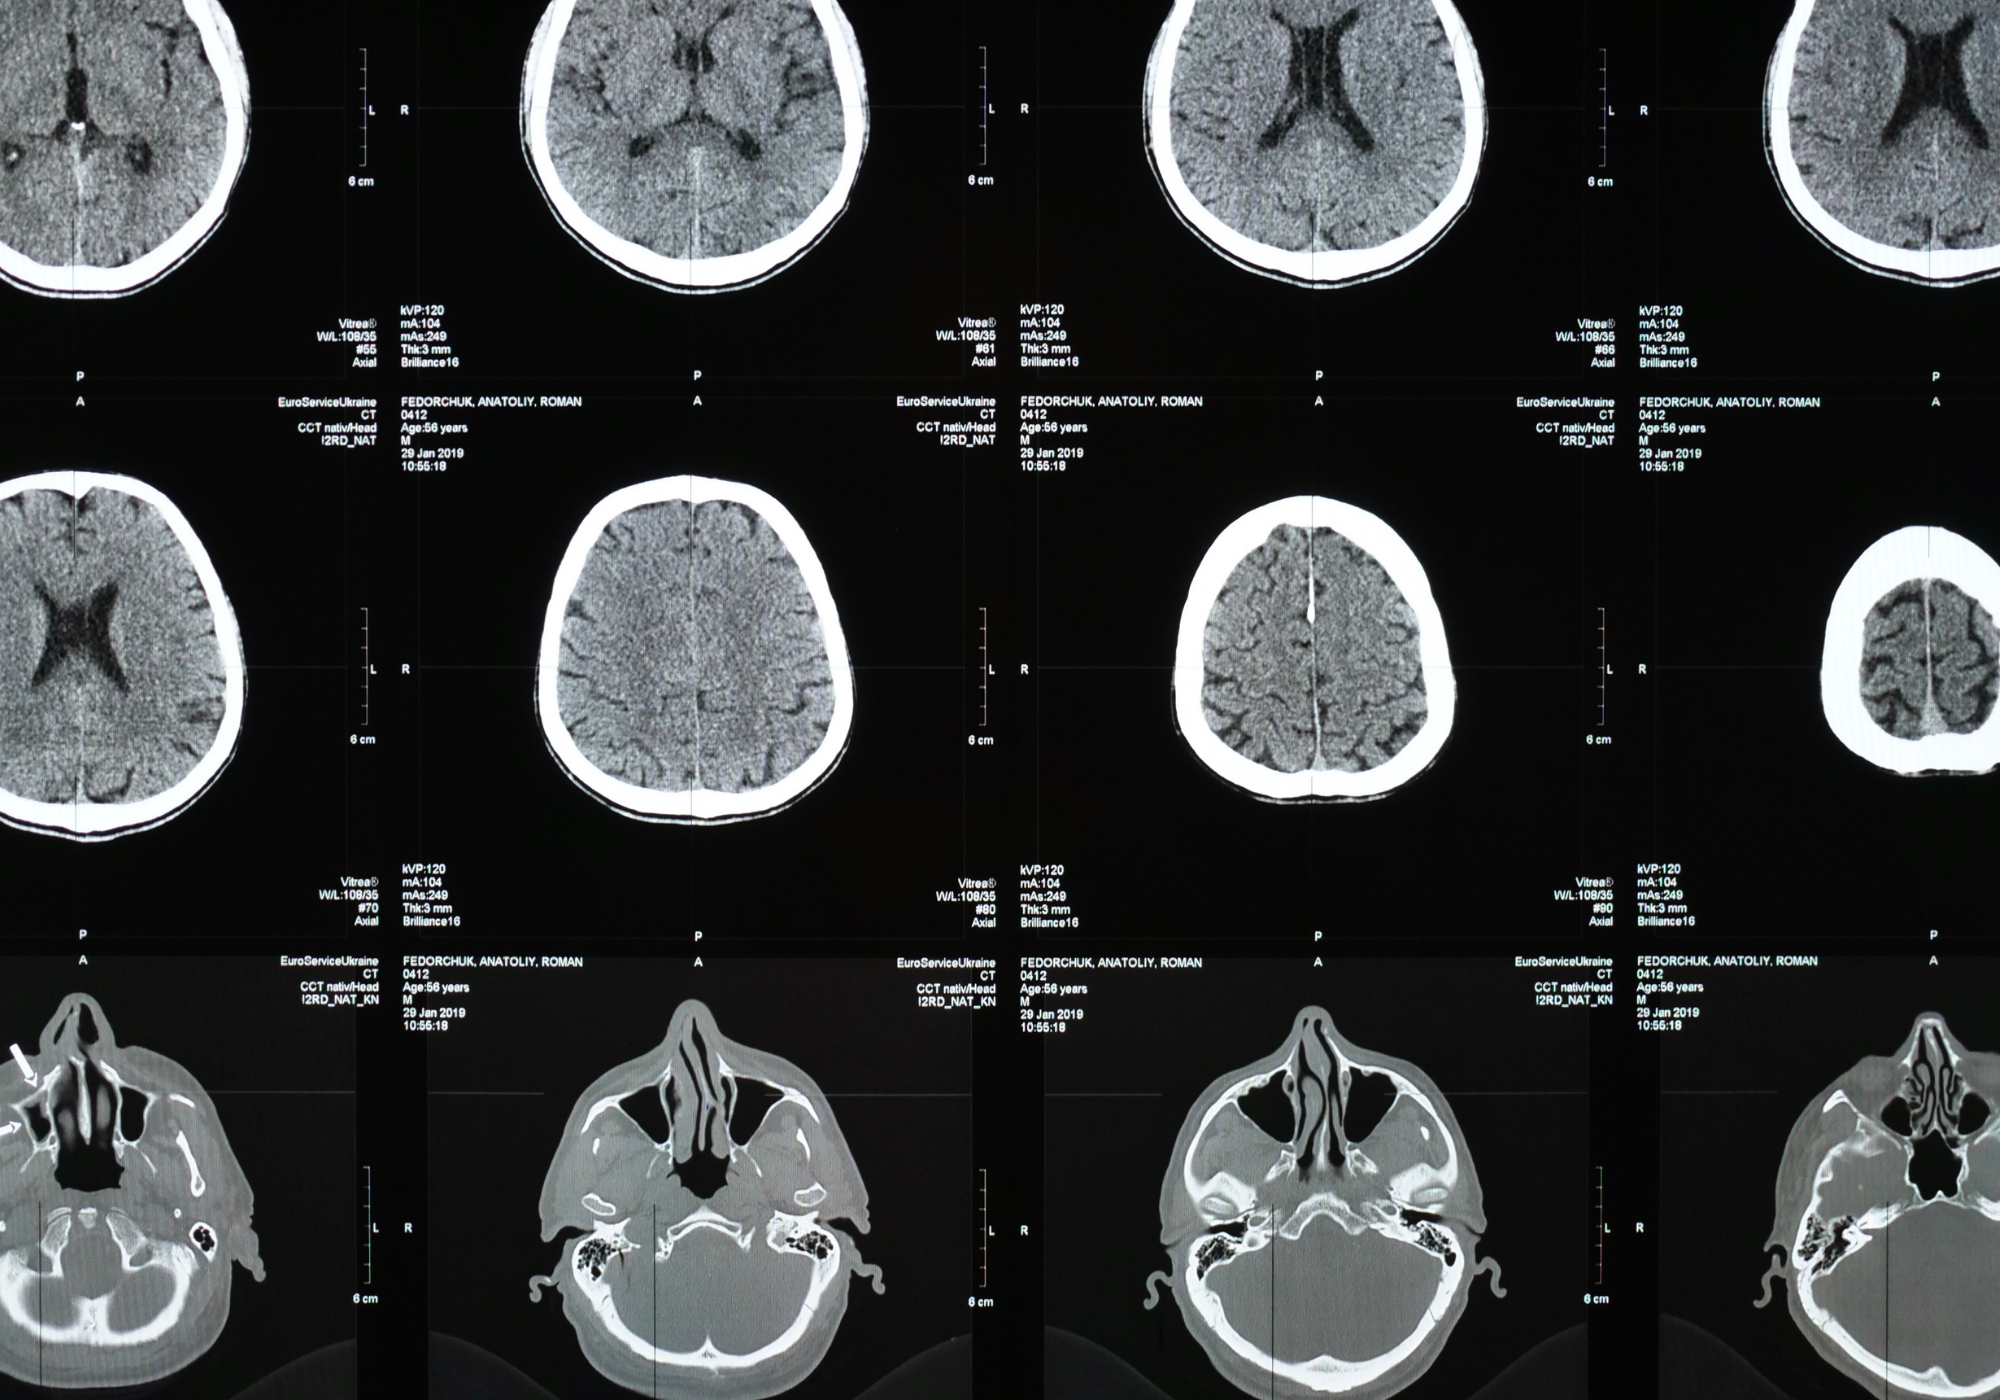

CT/CTA Scan

WHAT IS COMPUTED TOMOGRAPHY (CT)?

Computed tomography (CT) is a sophisticated diagnostic imaging tool that utilizes spiral X-rays and computers to generate cross-sectional images of the body, including internal organs, bones, soft tissue, and blood vessels. CT scans help diagnose a wide range of diseases from head to toe. The cross-sectional images generated can be reformatted in multiple planes and can even generate 3D images that can be viewed on a computer monitor or transferred to electronic media. CT scanning is often the best method for detecting many different cancers since the images allow your doctor to confirm the presence of a tumor and determine its size and location. CT is fast, painless, noninvasive, and accurate.

A CT Angiography (CTA) scan is a special type of CT exam. It examines the blood vessels, particularly in the brain, neck, chest, and abdomen. The contrast material makes the blood vessels show up clearly in the images. CTAs are very helpful in revealing aneurysms and examining the narrowing of the arteries.

There are various types of CT exams available, covering various sections of the body: Abdominal, Cranial, Lumbosacral Spine, Orbit, and Thoracic. These scans focus on body parts (arms, chest, legs, pelvis, and stomach) or internal organs (adrenal glands, bladder, heart, intestines, kidneys, liver, lungs, and pancreas). In addition, it can also be used to study blood vessels (which are harder to detect due to their small size and ease of “blending” in with their immediate surroundings), bones, the spinal cord, and other joints and extremities. The procedure’s main function is to diagnose and inspect various infirmities in the body, such as disease, infection, masses, and tumors (such as colon cancer or heart disease), without having to cut into the patient’s body. It also helps medical professionals during biopsy procedures and is used as a guide for interventional diagnoses.